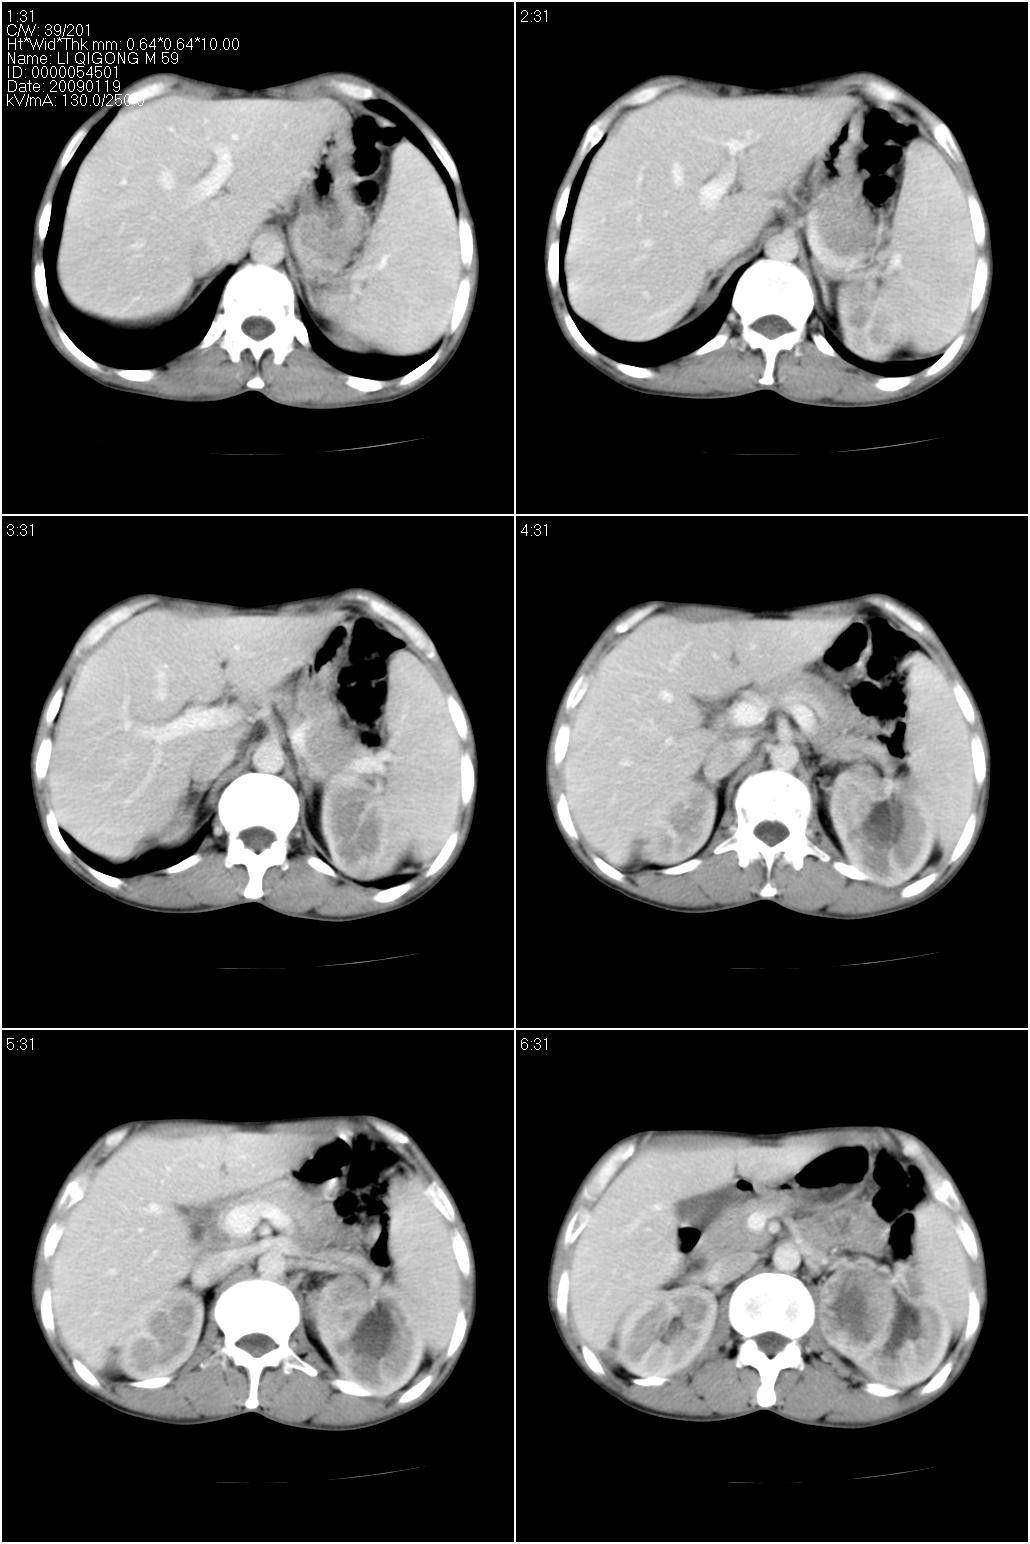

标题: CT17771:男性,59岁。体检发现左肾占位。 [打印本页]

男性,59岁。体检发现左肾占位。自诉无尿血、尿痛。

无痛无血尿,左肾实质占位,有明显强化,中心坏死不规则,应该肾癌无疑。

应该考虑左肾癌并肾盂积水

诊断依据:

1、中老年男性.

2、左肾占位,呈不均匀性强化,中央有无强化的坏死区。

3、左肾门旁有侧枝开放,提示左肾静脉癌栓形成可能。

4、患者自诉无血尿,但不一定镜下无血尿。

支持 考虑左肾癌并肾积水。